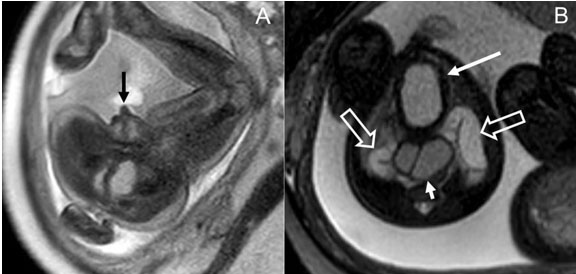

This was a female baby born to a 36-year-old mother G4P2, referred to the CFCC for twins with gastrointestinal and GU anomalies in one twin, including urinary bladder thickening and distension, dilated uterus with a septum, collecting systems and distal colon, and ambiguous likely female genitalia. Fetal MRI of twin B showed ambiguous, likely female, genitalia and prominent clitoris. There was hydrometrocolpos with a didelphys system. Additional syndromic features/anomalies included thick bladder wall, bilateral hydroureteronephrosis, and abnormally small rectum with posteriorly located anal dimple. In addition, there was dilatation of the descending colon with increased T2, decreased T1 signal suggestive of mixing of urine and stool. These findings were concerning for cloacal malformation (Figure 4).

Figure 4: Axial Single Shot Fast Spin Echo (A) and axial Steady State Free Precession (B) MR images of a 32 weeks 6 days fetus showing enlarged clitoris (black arrow in A), enlarged bladder with thickened wall (long white arrow in B), duplicated vagina (short white arrow in B), and bilateral hydroureter (open white arrows in B).